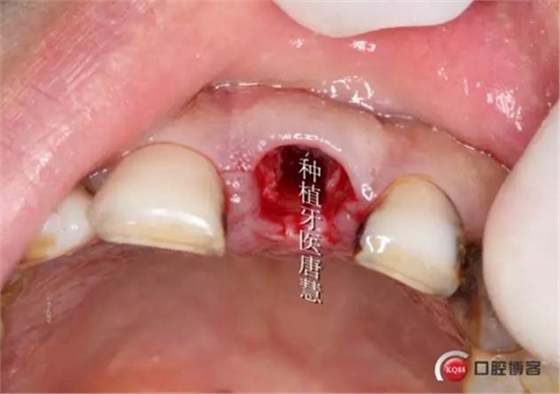

口內(nèi)情況

于殘根偏腭側(cè)備洞

拔除患牙